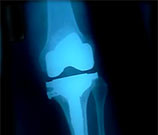

Cardiovascular Risk Up After Knee, Hip Replacement

Odds highest in the month following the procedure